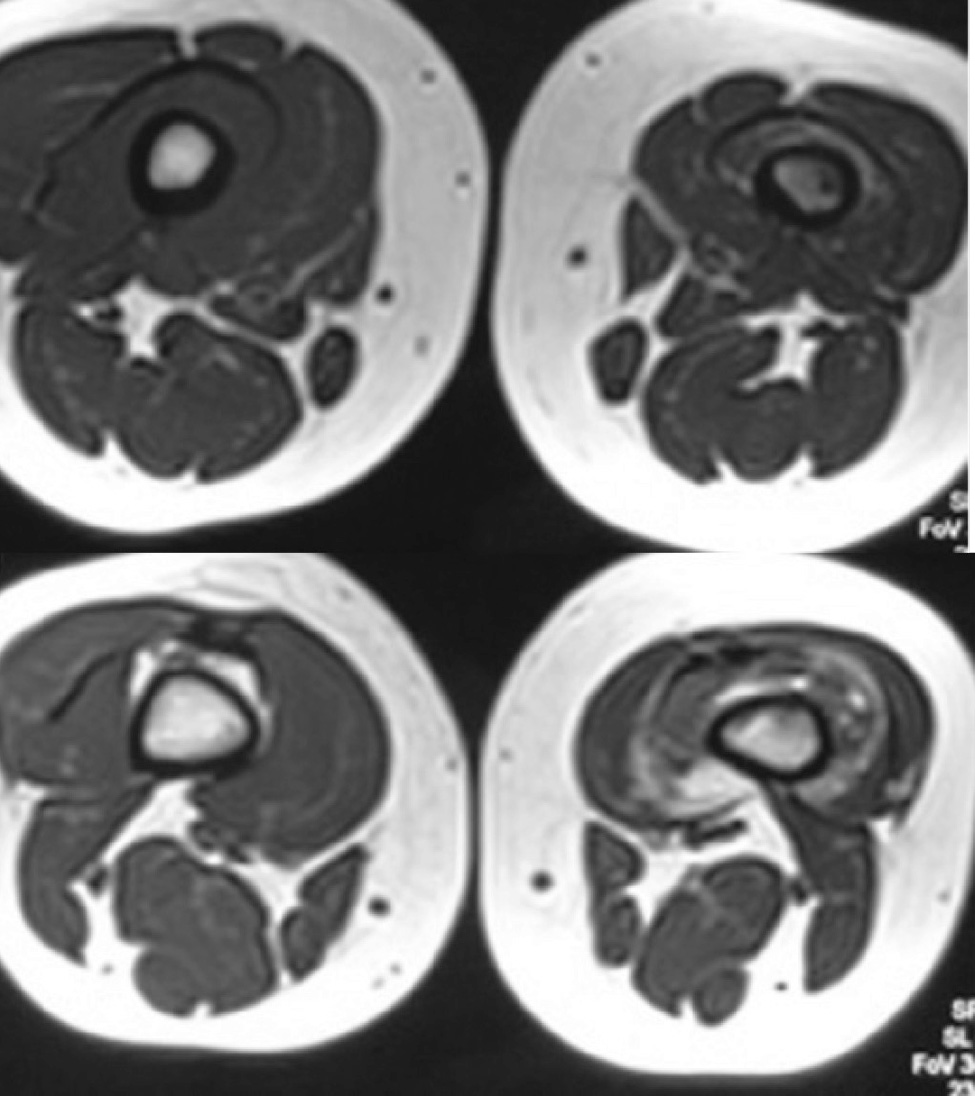

Recent gadolinium-enhanced and T1,T2 imaging showed a serpiginous enhancing lesion which contained signal void areas in 1/3 distal of thigh involving vastus intermedius and surrounded the femur without involving other adjacent muscles accompanying with atrophic changes and fatty changes in vastus intermedius muscle. It was extended to supra patellar pouch and was accompanied with adjacent heterogenous bone marrow signal and edema without evidence of cortical destruction or periosteal reaction with cortical thickening (Figure 2). On Doppler ultrasound, a heterogeneous hyperechoic soft tissue mass, containing vascular tissue and venous flow in distal left thigh with extension to supra patellar pouch was seen. According to MRI and Doppler ultrasound, findings were suggestive of probable hemangiom with adjacent secondary bony changes.

Figure 2. MRI showing a serpiginous soft tissue mass containing signal void areas with extension to knee joint with bone marrow edema and atrophy of vastus intermedius with fatty changes.  Axial T1W and T2W (a,b) and sagittal STIR  (c)  images.